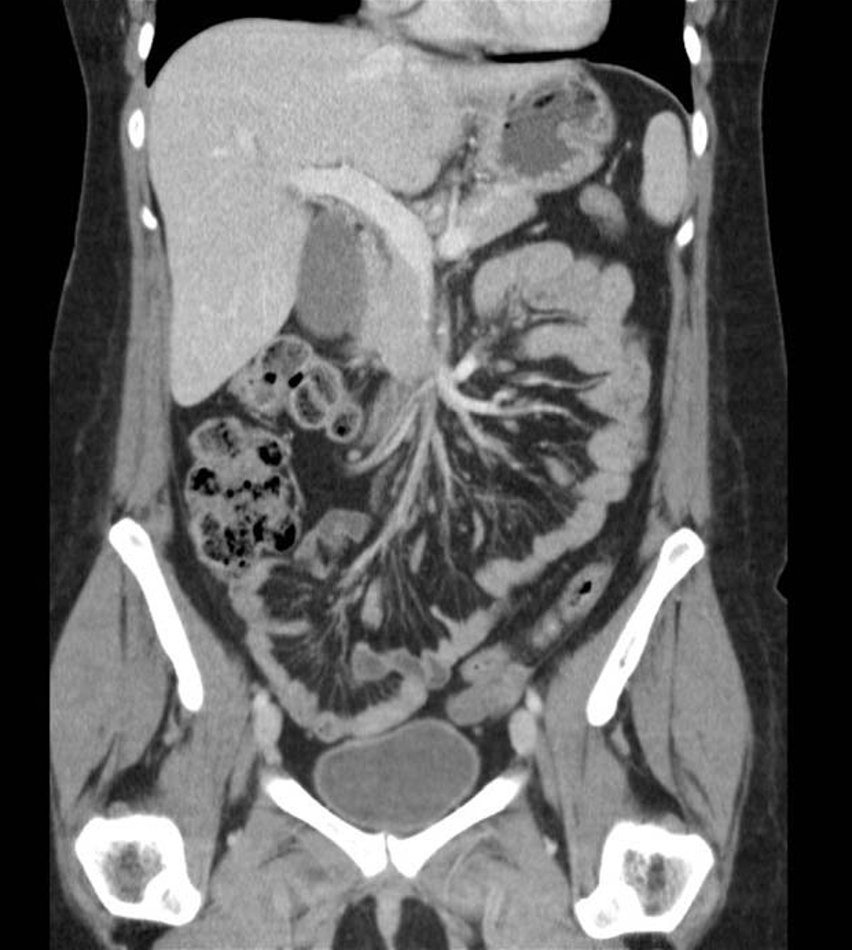

Miltraume:

20

Q

Diagnose?